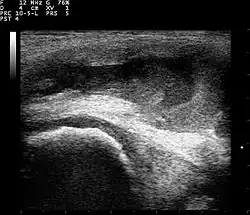

Ultrasound image of knee

Ultrasound

Ultrasound imaging may be used by your doctor in their office as a diagnostic tool to better visualize the effusion and its size. This can also be an effective tool to guide treatment such as a joint aspiration.[10]